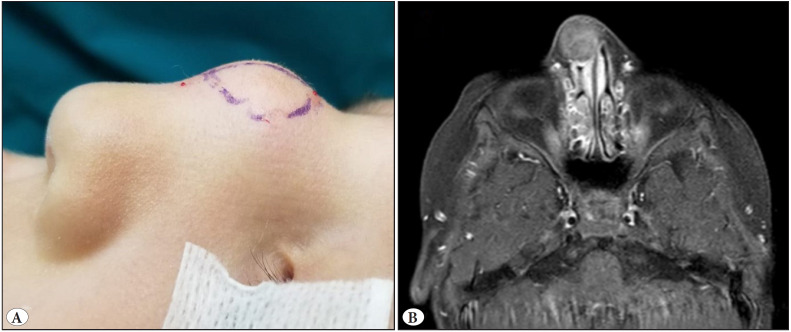

Case report: A 4-year-old child with a growth on the nasal dorsum since birth was diagnosed with nasal glial heterotopia/nasal glioma. The lesion showed a sclerotic fibroma/collagenoma-like storiform pattern with entrapped glial tissue that was S100 and GFAP positive.